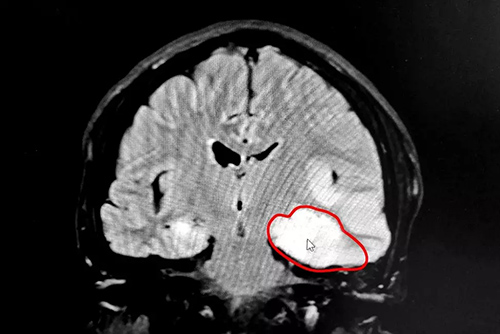

CT檢查結(jié)果顯示,患者頭顱左側(cè)顳枕頂葉見彌漫性大片狀低密度影,其中左側(cè)枕葉可見團塊狀稍高密度影,臨近左側(cè)側(cè)腦室受壓變窄,中線結(jié)構(gòu)向右側(cè)移位,其內(nèi)腦溝消失,腦組織腫脹。據(jù)此,診斷患者張先生為大面積腦梗。

▲CT檢查顯示,患者左側(cè)顳枕頂葉大面積腦梗